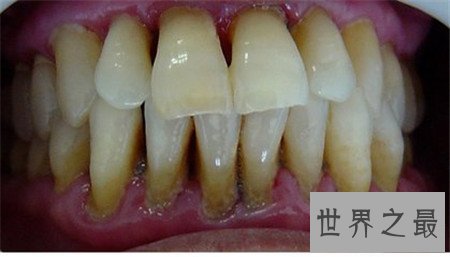

牙龈炎图片 快进来对比一下你有没有牙龈炎

牙疼不是病,疼起来要人命,这句话真的很有道理,牙上的炎症虽然不严重,不会产生什么严重的后果,但是治疗的过程是痛苦又漫长的,而且牙痛的原因也有很多,牙龈炎就是其中一条,牙龈炎图片很严重,今天小编要为大家讲讲牙龈炎的治疗方法,一起来看看牙龈炎图片吧

上图为牙龈炎图片

正常的游离龈是很薄且紧贴牙面,牙龈炎的病理症状:龈缘充血发红、肿胀、松软,龈缘变厚,牙间乳头变为钝圆,与牙面不紧贴,而且龈沟加深,严重者附着龈可因组织水肿,点彩消失,表面光亮,龈缘可有糜烂或肉芽增生,龈袋溢脓。